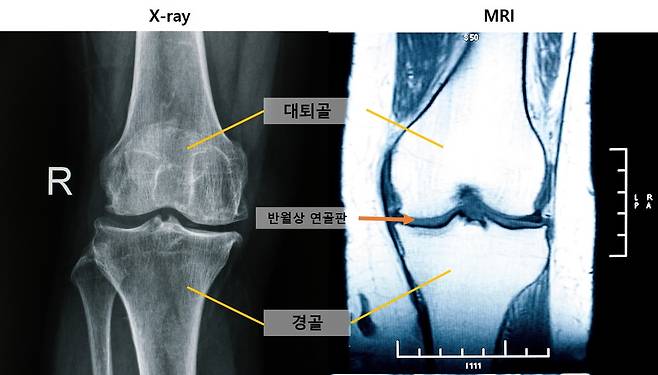

[헤럴드경제=김태열 건강의학 선임기자] 무릎 관절염을 조기에 발견할 수 있는 새로운 진단 지표가 확인됐다. 엑스레이에서 정상으로 진단된 무릎이라도, MRI에서 ‘중앙 대퇴골 연골 손상’ 소견이 관찰된다면 무릎 관절염이 이미 진행되고 있을 가능성이 높다는 사실을 국내 연구팀이 규명했다. 또한 MRI로 ‘내측 반월상 연골 돌출’이 관찰되면 관절염이 심각해질 위험이 높은 것으로 나타났다.

무릎 관절염 초기에는 연부조직(연골, 반월상 연골판 등)에서 먼저 변화가 발생하지만, 일반적으로 진단에 활용되는 엑스레이로는 이런 변화를 일찍 파악하는 데 한계가 있다. 연부조직을 관찰하기 용이한 MRI는 접근성이 떨어지며, 이처럼 서로 다른 특성을 가진 두 검사 방법의 연관성을 장기적으로 분석한 연구는 드물었다.

연구팀은 엑스레이로 평가한 관절염 진행 단계(0~4기)에 따른 주요 MRI 소견을 최대 7년간 추적 관찰했다. 그 결과, 관절염 진행 시 가장 먼저 나타나는 변화는 ‘중앙 대퇴골 연골 손상’이었다. 이 손상은 엑스레이에서 정상으로 여겨지는 관절염 0기부터 관찰되어, MRI가 무릎 관절염 초기 변화를 확인하는 데 중요한 도구임을 보여줬다.

또한, 관절염 진행 위험의 가장 강력한 예측 인자는 ‘반월상 연골 탈출’이었다. 추적 관찰 시간은 유의미한 연관성이 없어, 시간 경과보다는 무릎의 구조적 변화가 관절염 진행을 주로 유도하는 것으로 확인됐다. 한편, 관절염 진행에 따라 MRI상 무릎 중앙에서는 연골·반월상 연골판·뼈, 후방에서는 반월상 연골판·연골·뼈 순서로 손상 양상에 차이가 있었다.